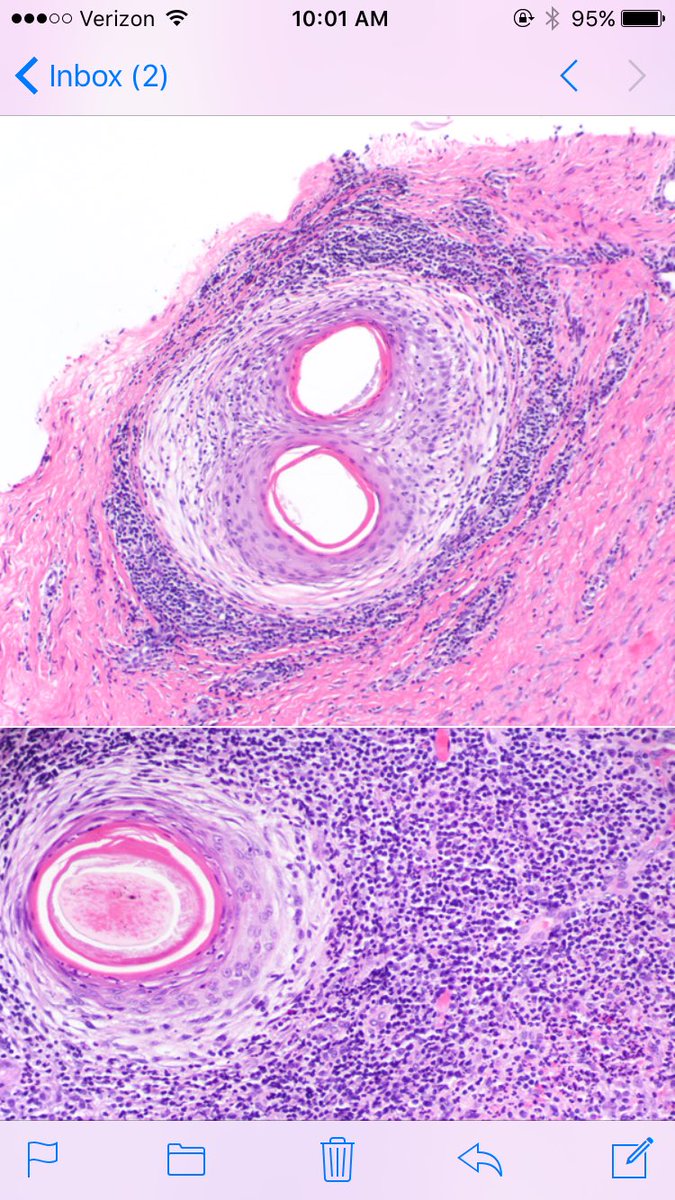

Follic. decalvans: not specific disease--PATTERN of very inflam cicat alop, usually from CCCA or LPP. Polytrichia (fused infundibula common)

LenSperling's tweet image. Follic. decalvans: not specific disease--PATTERN of very inflam cicat alop, usually from CCCA or LPP. Polytrichia (fused infundibula common)